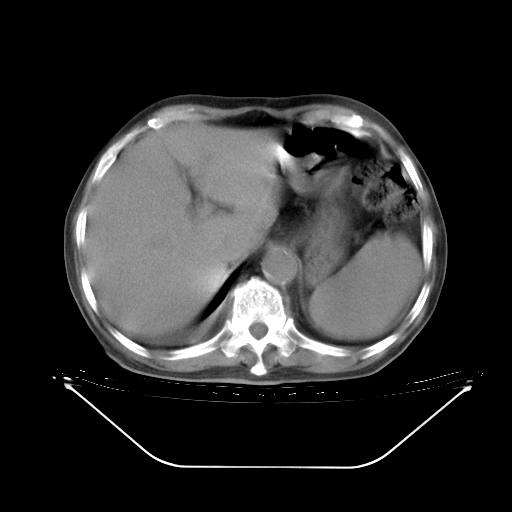

胸腹部CT,诊断意见:左上肺叶钙化灶、左侧胸膜局限性增厚并钙化、胆囊炎。描述部分肺组织呈磨玻璃样改变。

今天复查肺部CT,发现双肺广泛磨玻璃样改变。所以我把3月19日和5月9日相隔50天的肺部CT上传。请大家会诊。

5月9日肺部CT(在4月27日齐鲁医院肺部CT描述部分肺组织磨玻璃样改变,12天后肺组织广泛磨玻璃样改变)